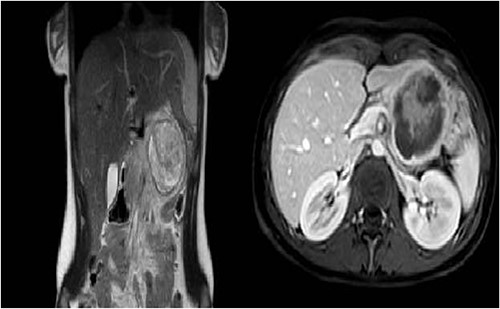

After obtaining the informed consent by the patient and her parents, a surgical procedure was planned using the ‘da Vinci Xi’ robotic platform. The patient was positioned in a reverse Trendelenburg position, 15° right tilt with a gel pad placed under the left flank; used the Veress technique, trocar placement was as follows: AirSeal 12-mm trocar (A) in the left iliac fossa, four 8-mm robotic trocars along the umbilical line, 7 mm distant to each other, being the abdominal surface limited due to the paediatric condition (Fig. 2).

Placement of trocars. The ports for the camera (C), robotic arms (R1–R3) and the assistant port (A) are shown.